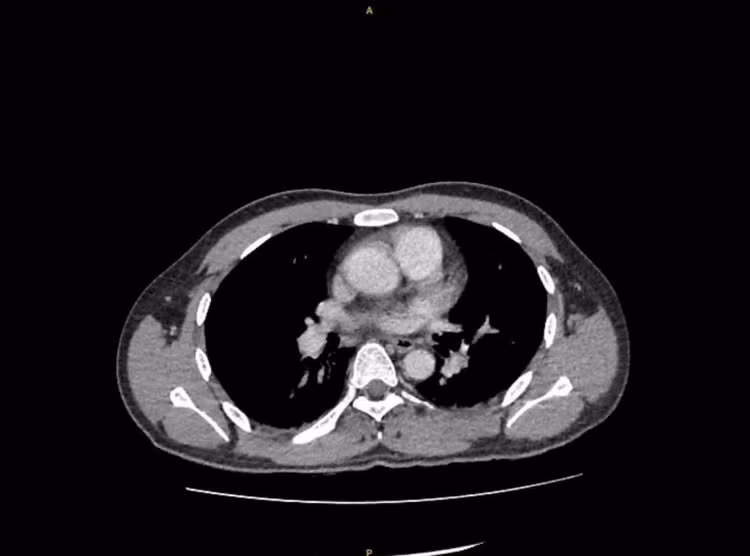

Hình ảnh phim CT trước mổ cho thấy thận có sỏi niệu quản bị ứ nước - Ảnh BVCC

Kết quả CT-scan bụng cho thấy có một viên sỏi nằm ở niệu quản trái đoạn lưng, gây tắc nghẽn hoàn toàn đường thoát nước tiểu - đây chính là thủ phạm khiến thận trái bị ứ và nhiễm trùng.

Các xét nghiệm máu, nước tiểu và hình ảnh học cho thấy chỉ số nhiễm trùng tăng cao, có dấu hiệu thận trái đã bị ứ mủ và chức năng của thận bị suy giảm.